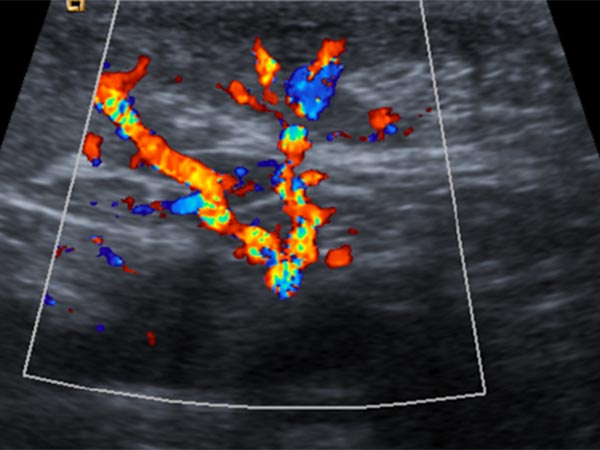

In der B-Bild-Sonographie (Bild oben) ist der Tumor relativ homogen, echoarm und klar solide, nicht komprimierbar. Die farbkodierte Duplexsonographie (Bild unten) zeigt eine starke Perfusion durch multiple arterielle Gefäße. Dies spricht für einen angeborenen vaskulären Tumor, in diesem Fall in Kombination mit dem bläulichen Erscheinungsbild für den Sonderfall eines kongenitalen Hämangioms.

Die Kontrollsonographie (FKDS) im 4. Lebensmonat zeigt keine Veränderung der Echogenität, insbesondere keine Zeichen einer Involution. Weiterhin starke Perfusion und keine Zunahme der Echogenität, wie das bei einem rasch involutierenden kongenitalen Hämangiom (RICH) der Fall wäre.